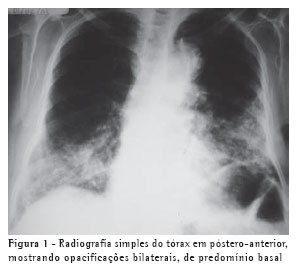

Uma dona de casa de 77 anos tivera havia sete anos diagnóstico de adenocarcinoma de mama, tendo sido submetida a mastectomia e radioterapia. Permaneceu bem clinicamente por cerca de cinco anos, em acompanhamento regular com oncologista, sem evidências de recidiva da doença. Havia dois anos começara a apresentar discreta dispnéia, que havia piorado nos últimos três meses, com o surgimento de tosse seca. Perdeu cerca de 12 Kg nos últimos meses. Foram realizados exames de imagem (Figuras 1 e 2). Seus antecedentes incluíam uma cirurgia anti-refluxo gastresofágico havia doze anos, além de uma longa história de constipação intestinal, sendo usuária contumaz de laxantes. Fora fumante por 50 anos, de dois maços por dia, tendo cessado o tabagismo nos últimos quatro meses. Criava dois canários em sua casa, durante os últimos dez anos.

A radiologia simples mostra opacidades basais ou difusas ou, eventualmente, uma massa solitária de baixa densidade, denominada "parafinoma".(5) A tomografia computadorizada de alta resolução revela consolidação de baixa atenuação, opacidade em vidro fosco ou padrão de pavimentação em mosaico,(1,5-8) como observado no presente caso.